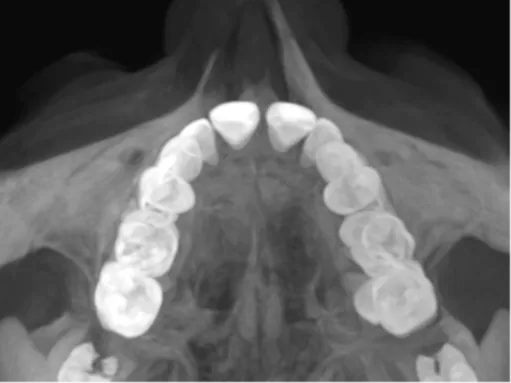

Invisalign Palatal Expander

Review your Invisalign Palatal Expander cases with us and benefit from a 50% discount on Invisalign Palatal Expander until 30 April.

TUTORIALS FOR THE INVISALIGN PALATAL EXPANDER